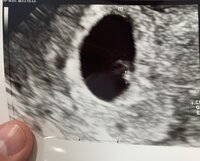

Mutta täytyy sanoa, että oli hiukan eri kattoa monitorista tommosta 2mm kaveria, kun esikoisesta käytiin 6+6 ja pituutta oli silloin 8.6mm

Ensimmäinen kuva on tosiaan tämän päivän pikkukaverista vk 5+5 ja alempi esikoisesta 6+6. Onneksi ties mitä etsiä monitorilta niin ei tullut turhaan panikoitua